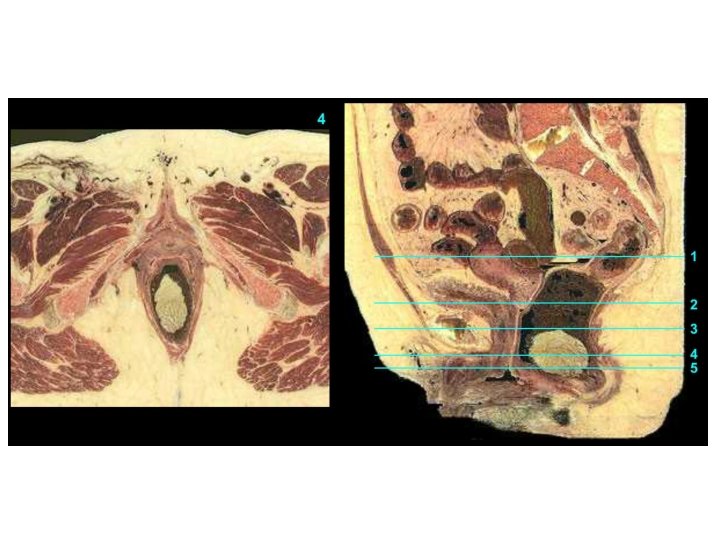

Vagina Excavatio vesicouterina Peritoneum Excavatio rectouterina Uterus Portio vaginalis cervicis Vesica urinaria Portio supravaginalis cervicis Fornix vaginae, Pars posterior Fornix vaginae, Pars anterior Vagina, Paries anterior Rectum Urethra Septum rectovaginale Septum vesicovaginale Vagina, Paries posterior Ostium vaginae Vestibulum vaginae Diaphragma urogenitale